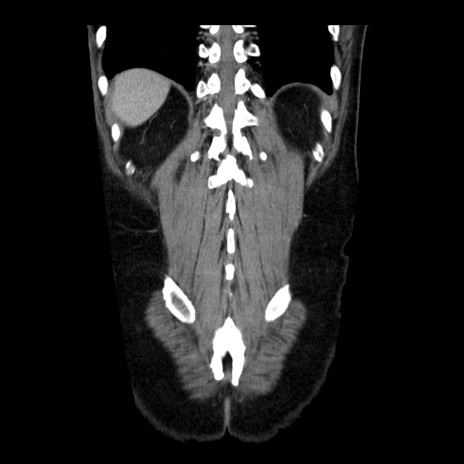

症例29(冠状断像)

【症例】40歳代男性

【現病歴】2日前から胃痛あり。徐々に周期的な激痛に変化した。本日になっても激痛があるため受診。

【身体所見】意識清明、BT 38-39℃台あり、腹部:膨満、やや硬、右下腹部に圧痛あり。

【データ】WBC 8500、CRP 23.26